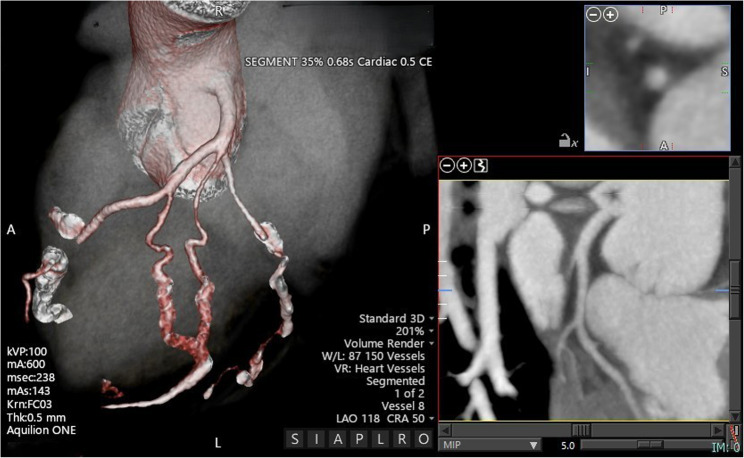

35岁男性,无明显心血管病史,心悸复发。最初的超声心动图评估显示偏心左心室肥厚,轻度收缩功能障碍,怀疑室间隔缺损,二尖瓣主动脉瓣和右心室扩张。经食管超声心动图显示右冠状窦动脉瘤样扩张伴主动脉-心房/心室瘘,经增强计算机断层血管造影进一步证实。冠状动脉造影发现单冠状动脉异常,左冠状动脉占优势,右冠状动脉缺失。手术修复成功关闭瘘,术后主动脉返流轻微。随访一年,心脏尺寸和功能恢复正常,主动脉瓣返流稳定。基因测序未发现可识别的突变。由于与二尖瓣主动脉瓣和冠状动脉异常相关的并发症的潜在风险,建议定期监测。

A 35-year-old male, without significant cardiovascular history, presented with recurrent palpitations. Initial echocardiographic evaluation demonstrated eccentric left ventricular hypertrophy, mild systolic dysfunction, suspicion of a ventricular septal defect, bicuspid aortic valve, and right ventricular dilation. Transesophageal echocardiography revealed an aneurysmal dilation of the right coronary sinus with an aorto-atrial/ventricular fistula, further confirmed by contrast-enhanced computed tomography angiography. Coronary angiography identified a single anomalous coronary artery with left dominance and absence of the right coronary artery. Surgical repair successfully closed the fistula, with mild post-operative aortic regurgitation. Follow-up at one year indicated normalization of cardiac dimensions and function, with stable moderate aortic valve regurgitation. Genetic sequencing found no identifiable mutations. Regular monitoring was recommended due to the potential risk of complications related to the bicuspid aortic valve and coronary anomaly.